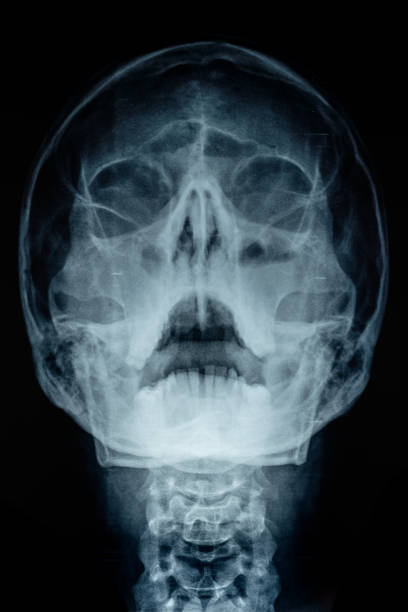

축농증은 균에 의한 감염으로 인해 발생하는 질환입니다. 이 질환은 목과 인후의 농양으로 나타나며, 열, 오한, 인후통, 목의 간질감 등의 증상이 나타납니다. 축농증 환자는 목의 농양 때문에 목이 간질간질하고 마른 기침이 나타날 수 있습니다. 이는 농양으로 인해 목의 조직이 염증이 생기고 부어오르면서, 기침을 할 때 목이 간질하고 마르게 느껴지기 때문입니다.

축농증은 증상이 심각하게 나타날 경우 수술을 통해 치료해야 할 수도 있습니다. 또한 항생제 치료와 적절한 휴식을 통해 증상을 완화시킬 수도 있습니다. 축농증은 치료하지 않으면 감염이 뇌에 번지거나 호흡곤란, 목의 굳은 증상 등 심각한 합병증을 유발할 수 있으므로, 증상이 나타날 경우 즉시 의학적인 상담과 치료가 필요합니다.